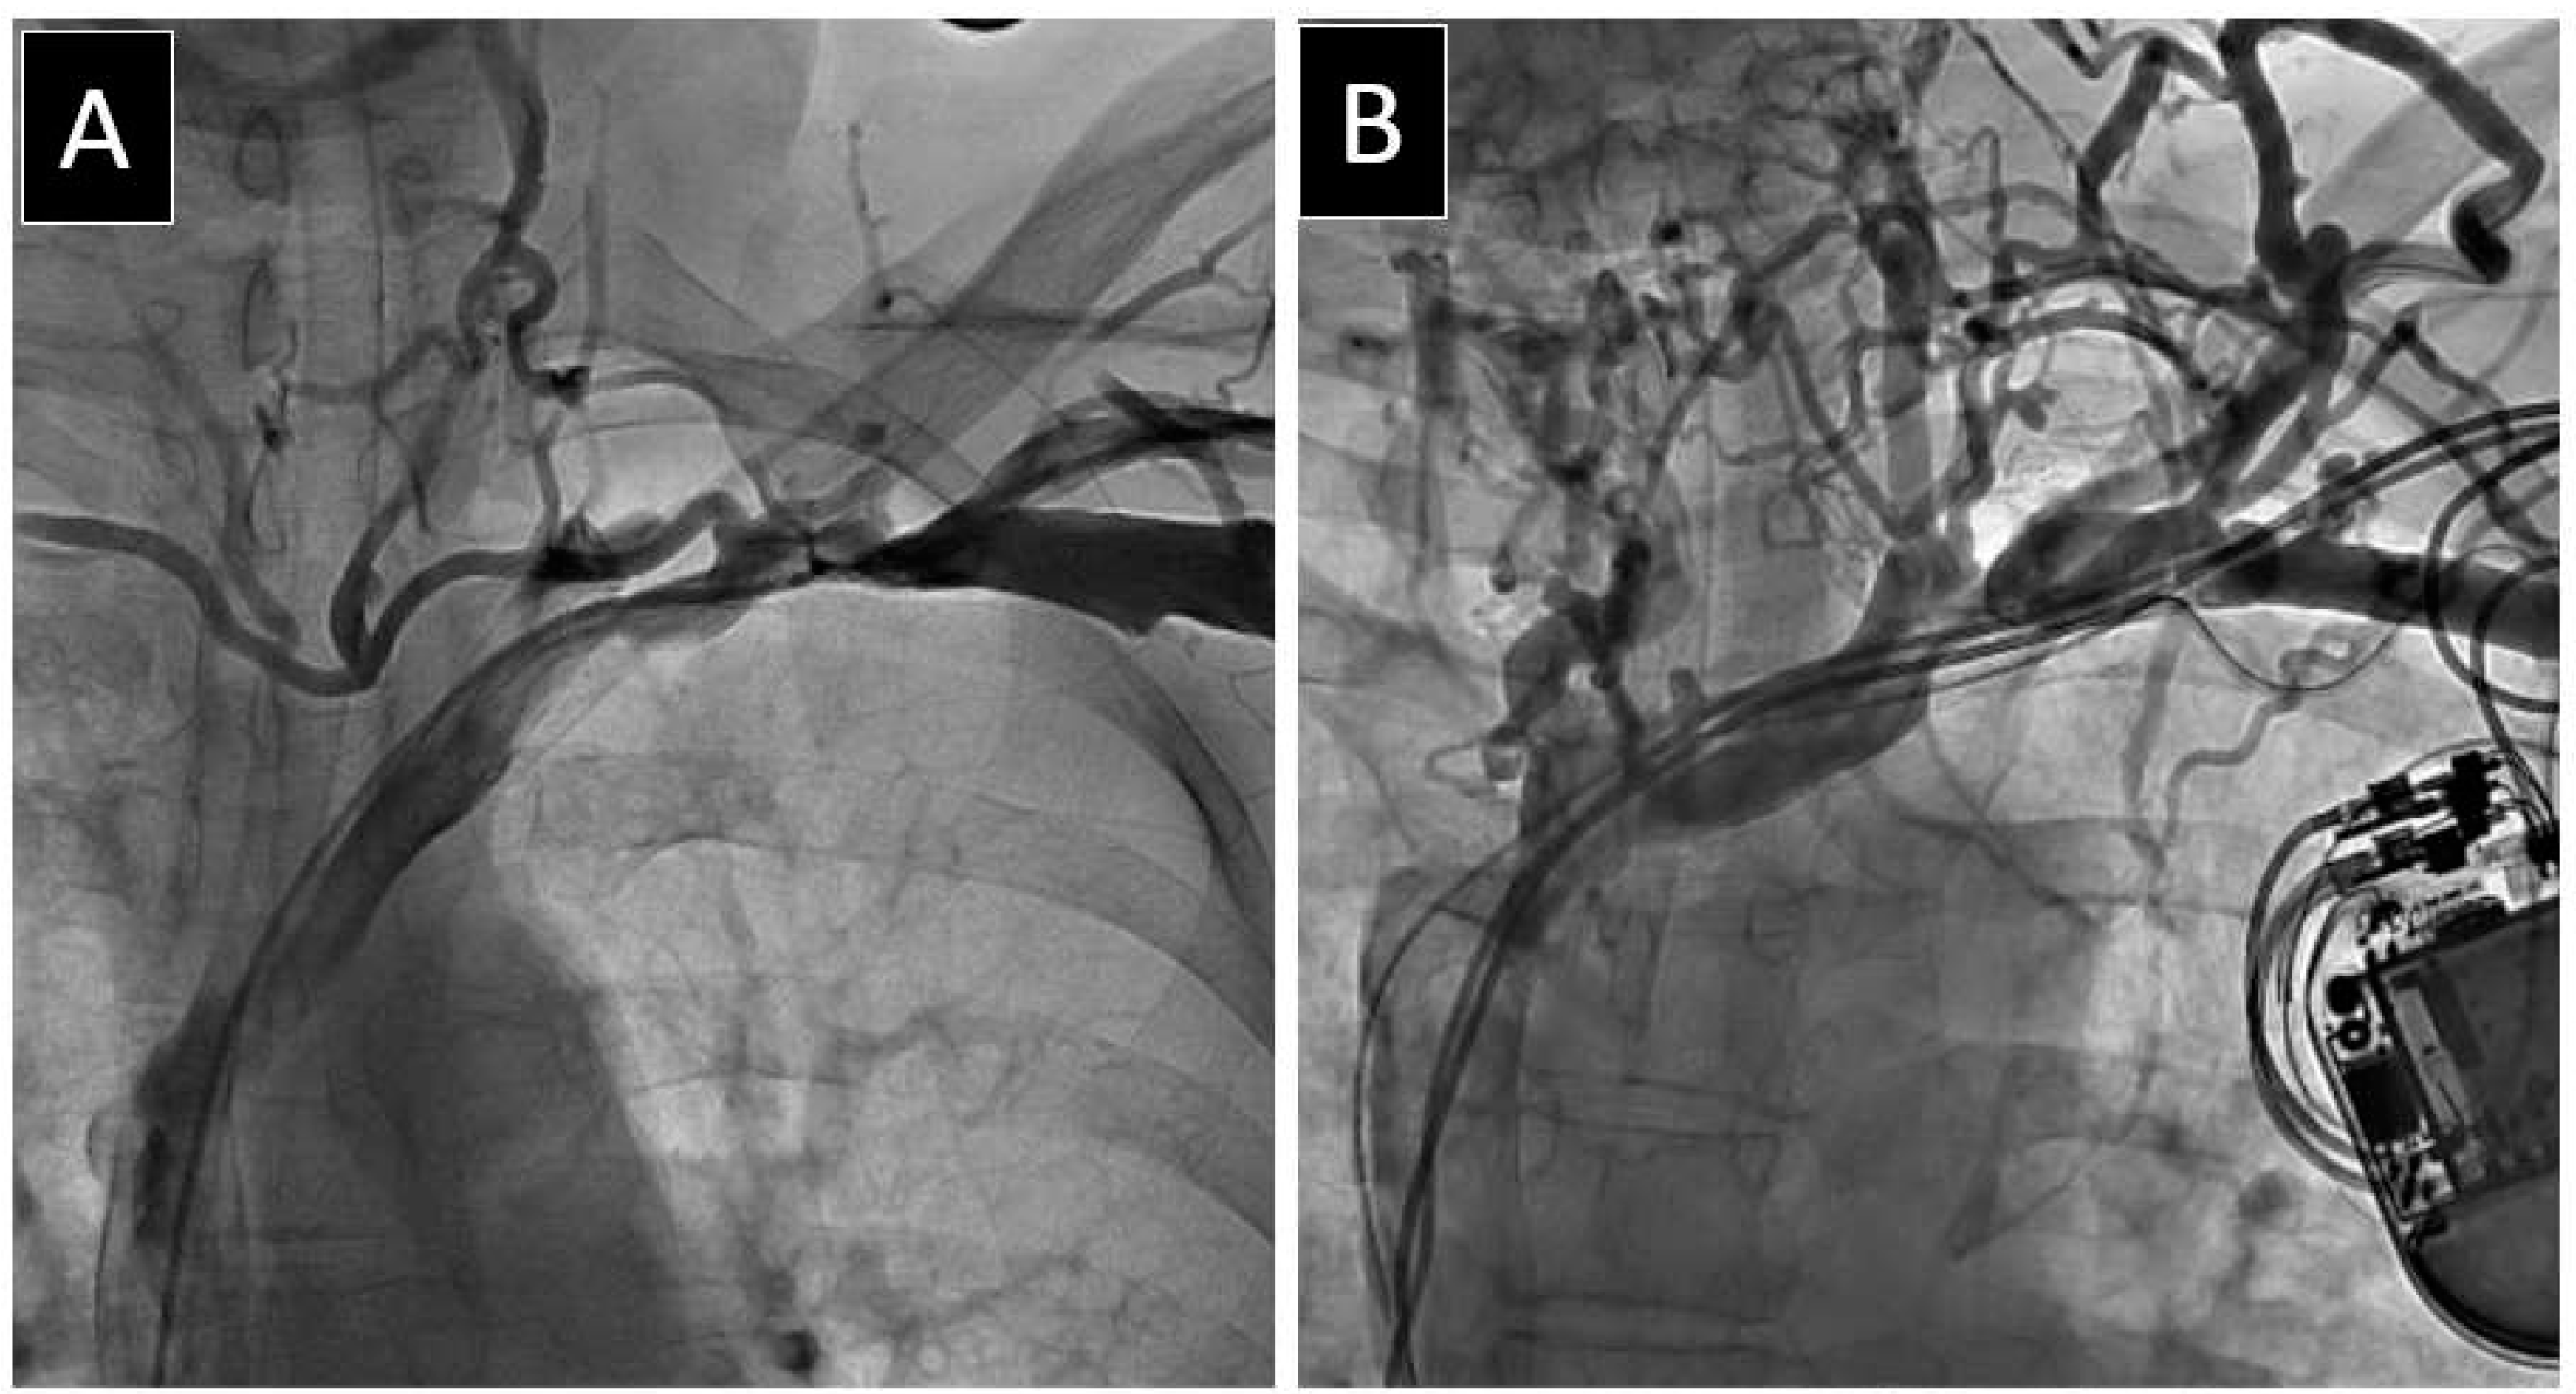

2.2. Venography Procedure

2.3. Lead Extraction Procedure